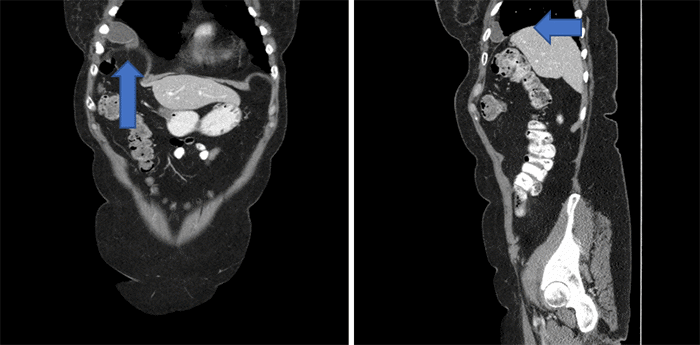

This case report represents one of the rarest documented instances of diaphragmatic hernia. Not only does it involve a case of spontaneous diaphragmatic rupture without a history of trauma, but it is also unique in occurring on the right side and exclusively involving the gallbladder. The patient, a 74-year-old female with interstitial lung disease, ER+ breast cancer, and hypothyroidism, underwent a contrast-enhanced CT abdomen/pelvis a year after completing a hysterectomy due to a high-grade squamous intraepithelial lesion of her cervix. The scan revealed the gallbladder situated superior to the right hemidiaphragm, accompanied by right hemidiaphragm elevation.

Figure 1. CT Imaging of Chest, Abdomen, and Pelvis. Published with Permission

A) Coronal view showing the gallbladder above the diaphragm, and B) sagittal view showing the gallbladder above the diaphragm